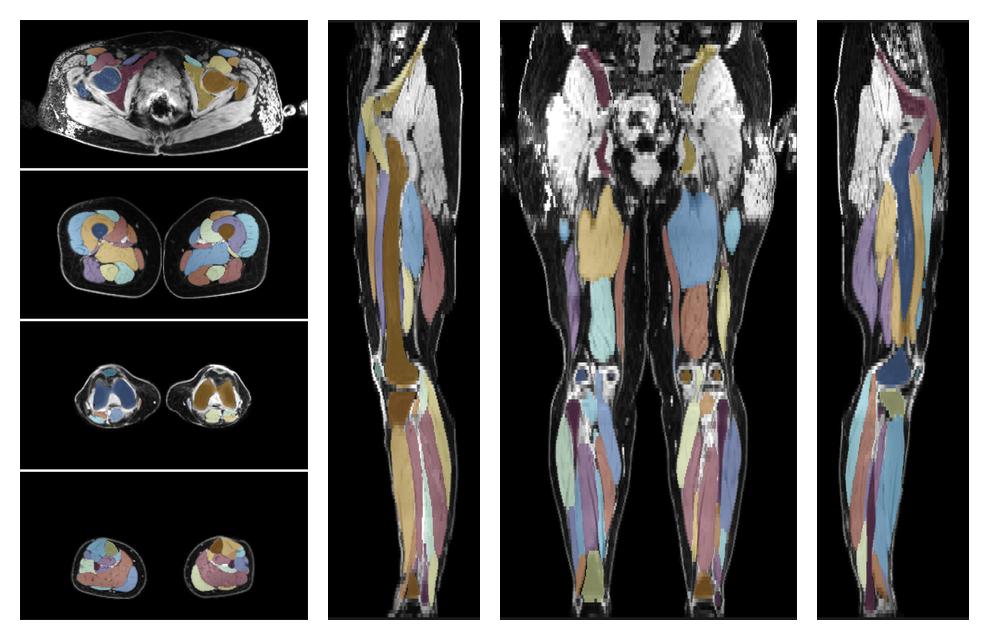

Muscle segmentation

Convolution neural network based (UNET) fiber automated muscle segmentation, for information look here».

• 3D volume render of automated muscle segmentation.

3D render of automated muscle segmentation labels generated using a CNN UNET.

• Automated muscle and bone segmentation.

Overlay of automated muscle segmentation labels on dixon water image.